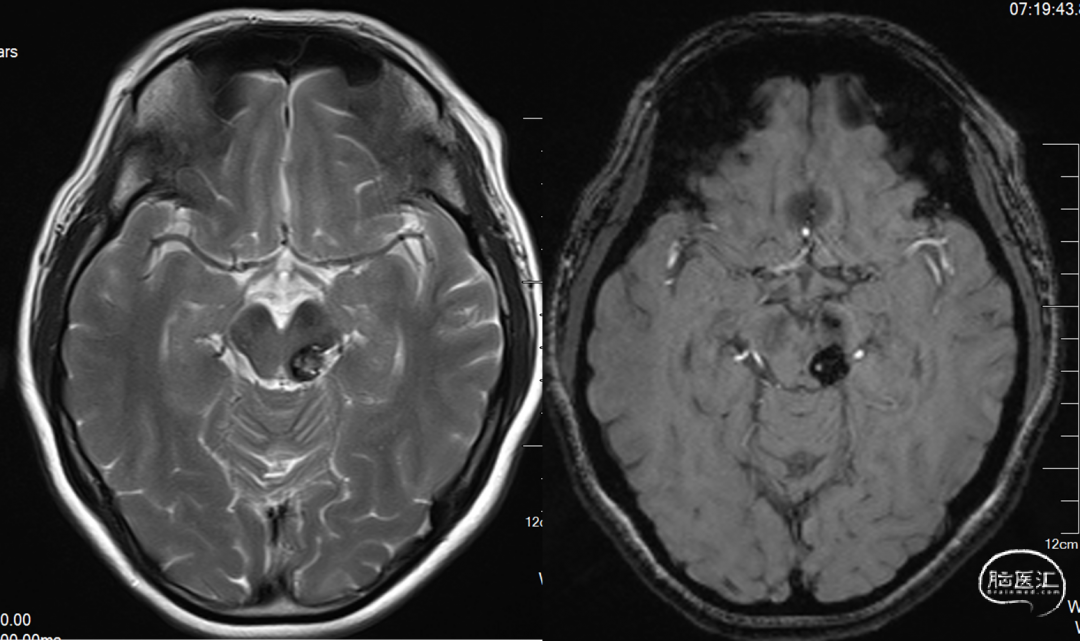

MRI 扫描:有边界,呈圆形。病灶在 T1 加权像呈等信号,在 T2 加权像或注射对比剂后呈高信号,病灶内有混杂低信号,病灶周围有环形低信号带。小型 (<1 cm) 以及非出血性海绵状血管瘤,磁敏感加权成像(SWI)的检出率更高。

患者,女,27岁,发现脑室旁海绵窦状血管瘤,是一种多发的海绵状血管瘤。反复出血两次,用显微镜手术。9天后复查,可见一定血丝,2个月后复查,很干净,病人无明显病灶。今年复查见对侧丘脑有一血肿,手术难度大。